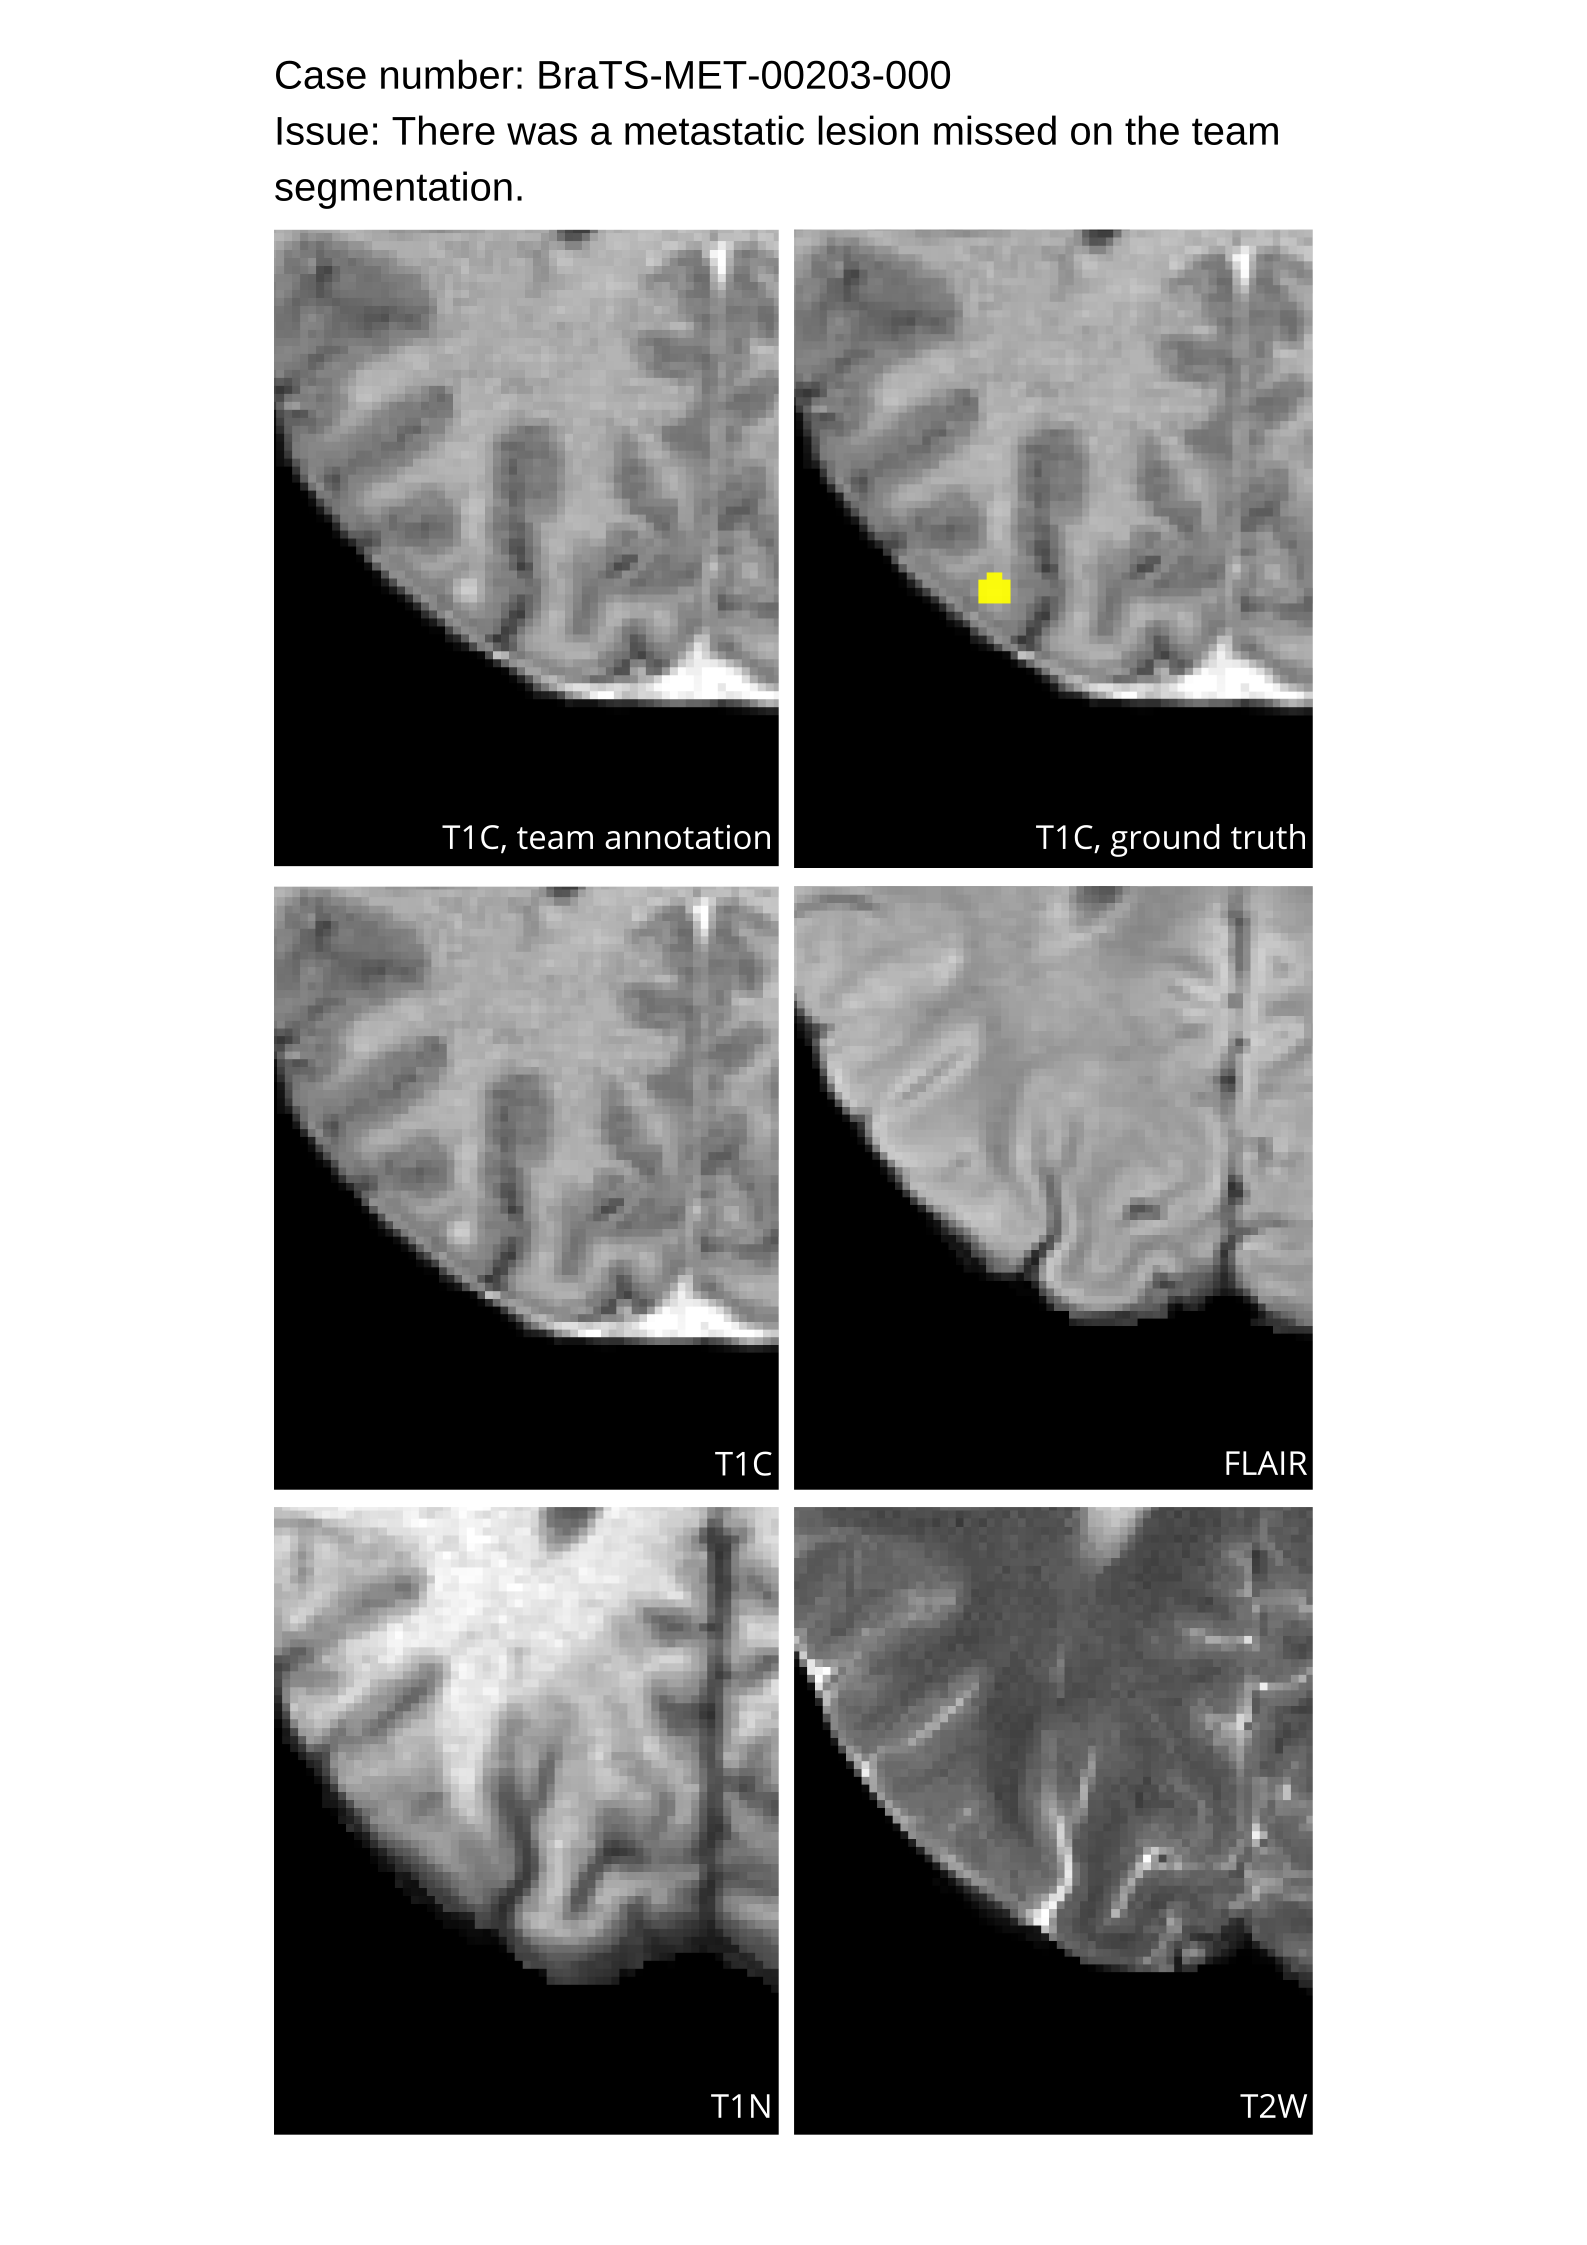

4.9 Common Errors of Automated Segmentations

Based on observations from previous BraTS challenges, common errors in automated segmentations were identified. The most typical errors in the current challenge included:

1. 1.

Automated algorithms missing small metastases. Enhancing metastasis was fused using the minority voting algorithm to aggregate all enhancing tumor voxels identified by the three algorithms. However, many small metastases were missed and were manually segmented by neuroradiology attendings.

2. 2.

Segmentation of white matter changes from microvascular disease. Peritumoral edema segmentations were checked by neuroradiology attendings and modified.

3. 3.

The segmentation of non-enhancing lesions that have intrinsic T1 hyperintensity. Voxels with intrinsic T1 hyperintensity were manually removed from ET segmentations.

These insights led to specific adjustments in the annotation process to enhance accuracy.